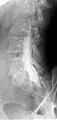

Myelography

Myelogram showing arachnoiditis in the lumbar spine.